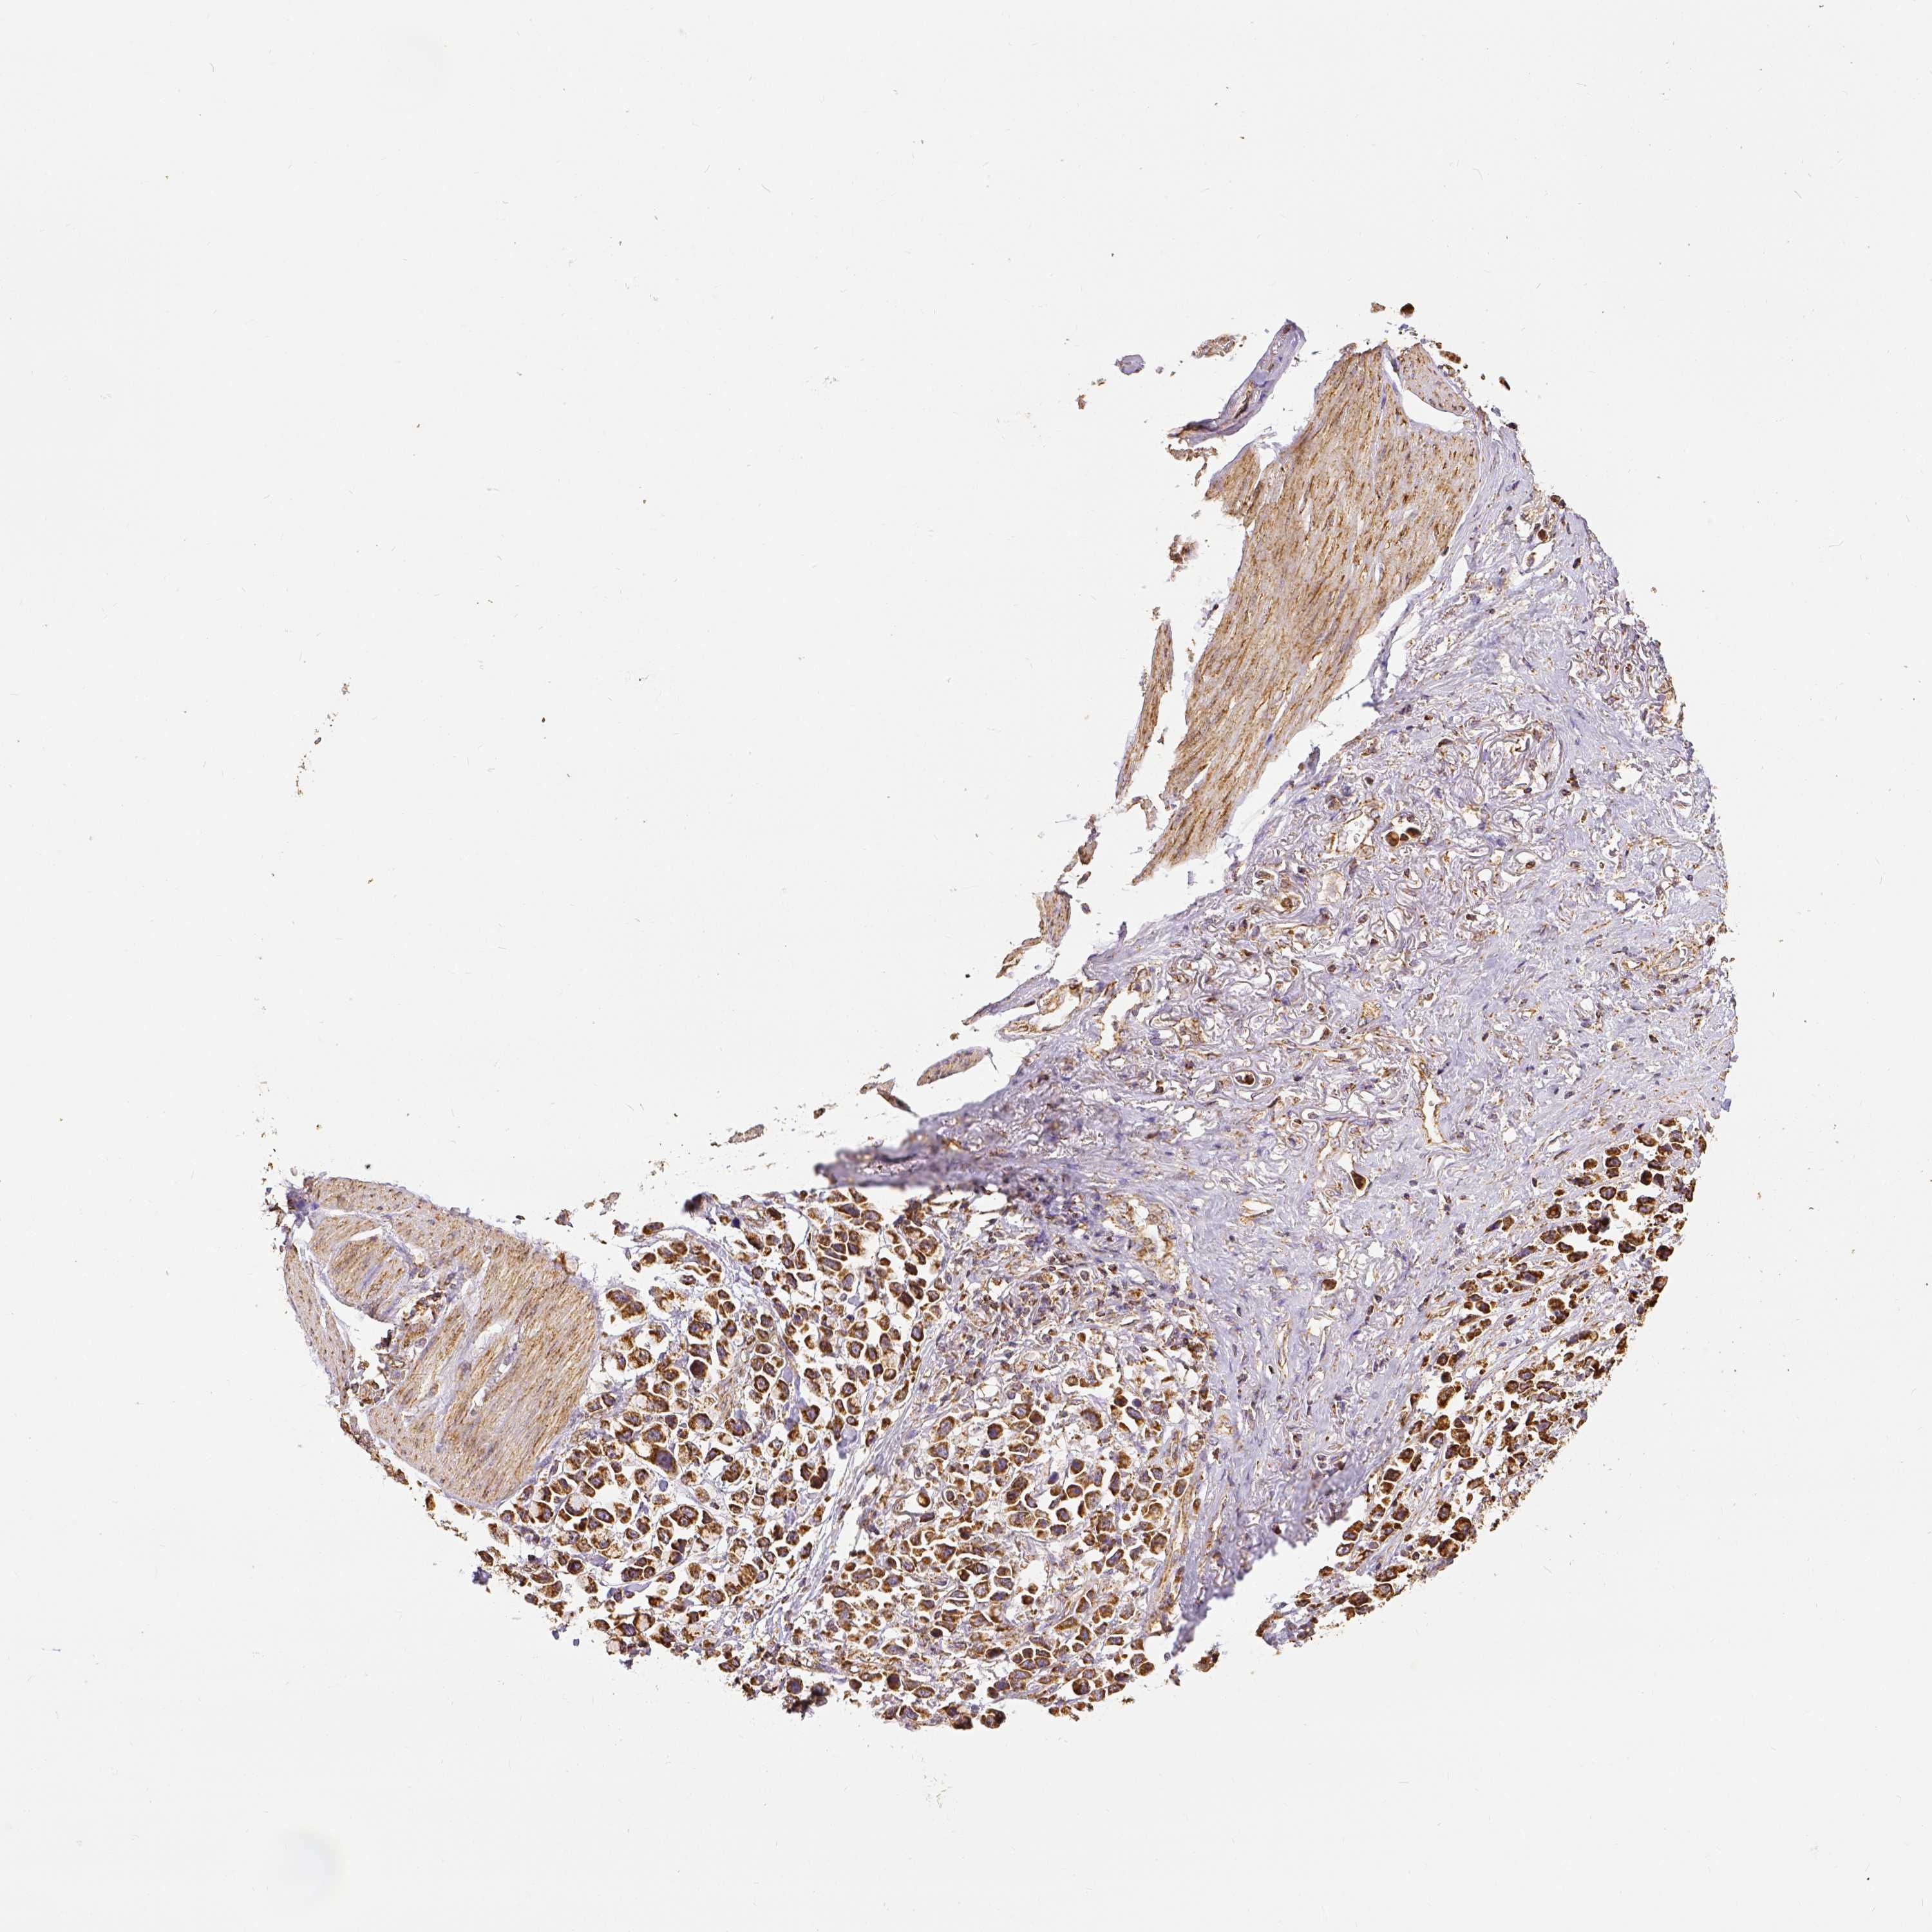

STOMACH CANCER - Protein expressioni

A mouse-over function shows sample information and annotation data. Click on an image to view it in a full screen mode. Samples can be filtered based on level of antibody staining by selecting one or several of the following categories: high, medium, low and not detected. The assay and annotation is described here.

Antibody stainingi

Antibody staining in the annotated cell types in the current human tissue is reported as not detected, low, medium, or high, based on conventional immunohistochemistry profiling in selected tissues. This score is based on the combination of the staining intensity and fraction of stained cells.

Each image is clickable and will lead to virtual microscopy that enables deeper exploration of all samples and also displays staining intensity scores, fraction scores and subcellular localization as well as patient and tissue information for each sample.

Adenocarcinoma, NOS

Adenocarcinoma, High grade